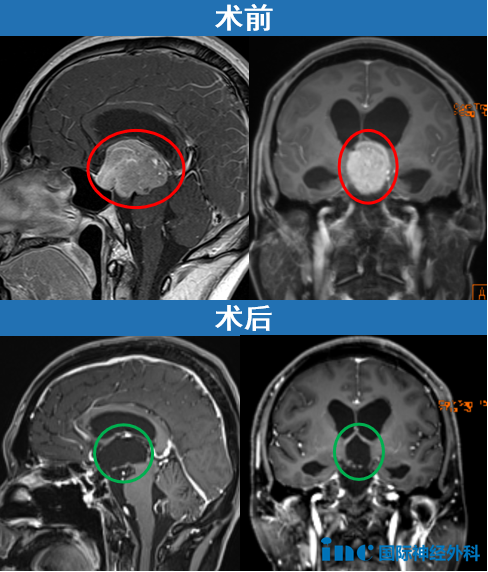

一位35岁男性患者因头痛就诊,伴随出现疲劳、食欲减退、注意力下降及行走不稳等症状。影像学检查显示鞍区及鞍上存在巨大垂体瘤,引发阻塞性脑积水,肿瘤已压迫脑干、第三脑室及中央导水管。面对较高的手术风险,患者积极寻求手术治疗方案。

在INC福洛里希教授主刀下,通过经鼻内镜手术成功切除了这一巨大垂体瘤。术后患者恢复良好,福洛里希教授表示:"这是一次十分具有挑战性的手术,我很高兴为你成功手术!" 针对脑脊液漏这一常见并发症,福洛里希教授指出:"在我们的临床实践中,脊索瘤经鼻内窥镜手术的脑脊液漏发生率传统约为50%,近年来通过技术进步已降至10%左右。"